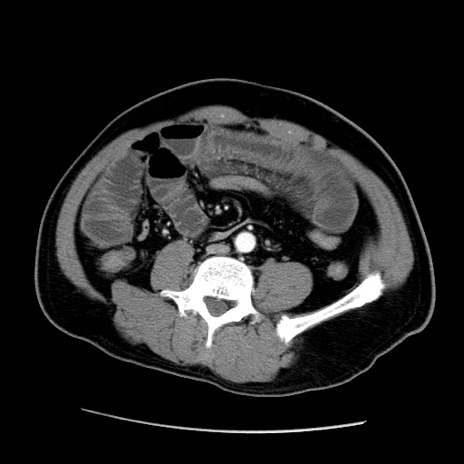

冠状断像